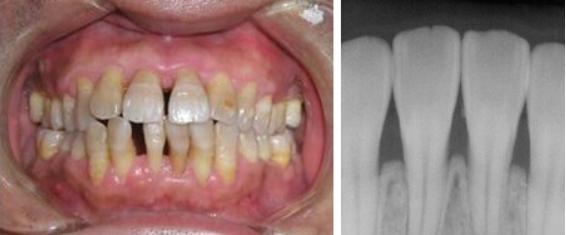

- 牙龈萎缩的初期,我们通过医疗手段给牙龈去除刺激,构建一个健康的牙周状态,牙龈是很可能自行恢复到比较自然健康的状态的。

- 牙龈萎缩的中期,我们可以用药物等手段帮助患者将牙龈萎缩的情况减轻缓解和控制,至少可以叫患者不会因为牙龈萎缩的问题影响用牙。但是这个阶段的牙龈已经无法恢复成它最初的样子了。

- 牙龈萎缩的晚期,想要将牙龈恢复到健康状态就几乎不可能了。如果牙齿已经出现了松动,甚至有将要脱落的迹象,有时即使通过治疗也无法保住病牙。

通常情况,我们对牙龈问题的治疗都是以重新构建健康的牙周环境为出发点,治疗或者改善牙周疾病为主要方法。争取给患者一个健康的牙周环境,一个健康的牙龈。

如果患者对牙龈的修复问题要求很高,我们也确实有一些尚未特别成熟的牙龈修复处理方式,例如使用有弹性的假牙龈,或者膜龈手术。